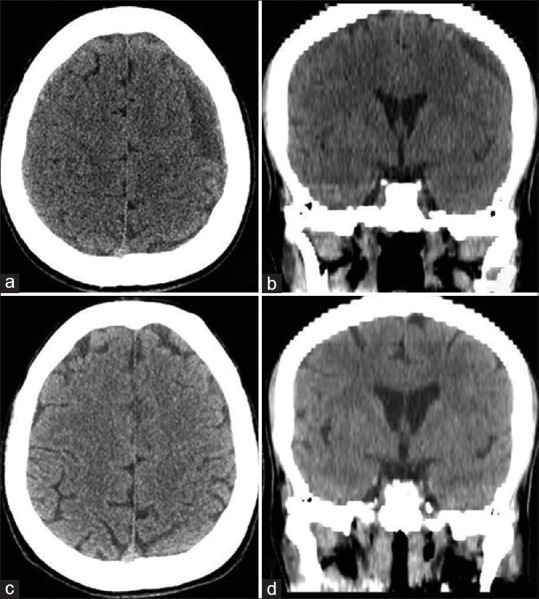

Subarachnoid-pleural fistula (SPF), a rare complication following transthoracic spinal surgery, results in the accumulation of cerebrospinal fluid (CSF) in the pleural space. Hindered spontaneous closure, attributed to negative pleural pressure, gives rise to CSF hypotension and subdural blood collections. Despite numerous reported cases, achieving consensus on management remains elusive. Treatment options encompass conservative measures, surgical repair, epidural blood patch, and diverse approaches such as multilayer dural closure or meningocele resection. Presented herein is a distinctive case following lateral thoracic meningocele surgery, where SPF-induced CSF hypotension found successful resolution through the innovative use of titanium hemostatic clips to occlude the meningocele. This novel approach, emphasizing the utility of titanium clips, deviates from conventional strategies. Surgical SPF exclusion, particularly leveraging titanium clips, emerges as a potential solution, effectively alleviating symptoms of CSF hypotension. The article also aims to present a personal experience, contributing an effective and alternative approach for the etiological treatment of thoracic meningocele.